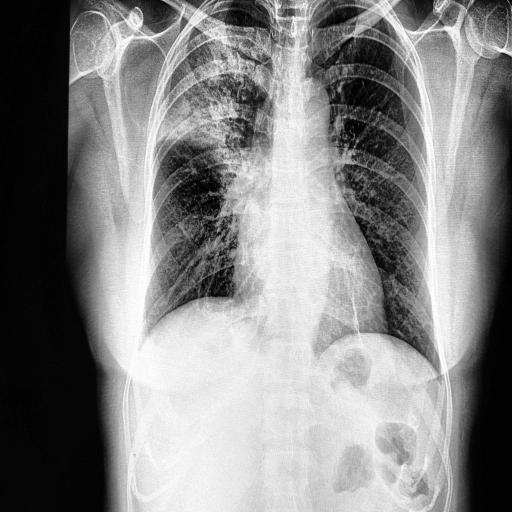

In this work, we only consider the CXR images in a frontal view, namely Poster anterior (PA) and Erect anteroposterior (AP). The first two databases in the above list comprise 520 such images. For the training purpose, we have used these images along with 520 CXR images of normal and pneumonia cases from COVID-19 Radiography Database (Kaggle) COVID19R73:online and Mendeley Chest X-ray Images kermany2018large . Figures 1(a) and 1(b) depicts the manually marked region of interest that distinguishes between COVID-19 and Pneumonia cases in CXR images. The above regions are marked by a radiologist after clinical evaluation of these CXR images.